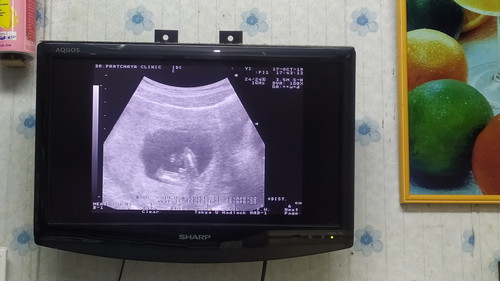

ก่อนจะตรวจเราบอกลูกอยากรู้เพศน้องแล้ว ตอนคุณแม่ไปซาวด์อ้าขาให้คุณหมอเห็นนะจร้ เป็นไงล่ะ สมใจอิแม่จร้ ผช นะจร้ รักๆๆ 15w5d